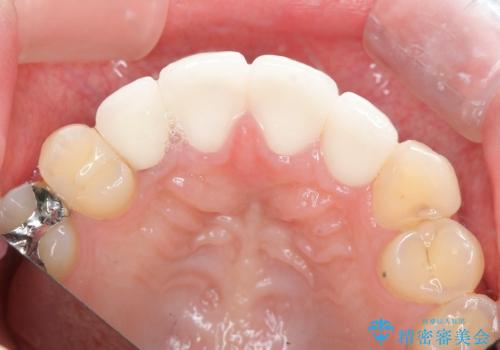

- 52.8万円(ジルコニアクラウン×4・仮歯×4)費用は治療当時の料金となります

レジン修復による充填は、劣化し、色調の変化による審美障害が生じることが多々あります。

ある程度の大きさになった充填物は、劣化の少ないセラミッククラウンにすることで色調の劣化を抑え、審美性を保つことができます。